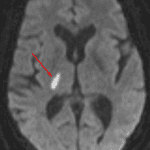

- Areas of hypoattenuation in the posterior limb of the right internal capsule, inferior left thalamus, right hemipons, and right cerebellar hemisphere

- Asymmetrically hyperdense appearance of the right internal carotid artery terminus and proximal right MCA

Small vessel infarcts involving the posterior limb of the right internal capsule, inferior left thalamus, right hemipons, and right cerebellar hemisphere, which are age-indeterminate in the absence of prior imaging for comparison. Consider MRI for further evaluation if there is clinical concern for acute infarct.

Asymmetrically hyperdense appearance of the right internal carotid artery terminus and proximal right MCA, which may be artifactual or could represent thrombus. Recommend correlation with CTA.